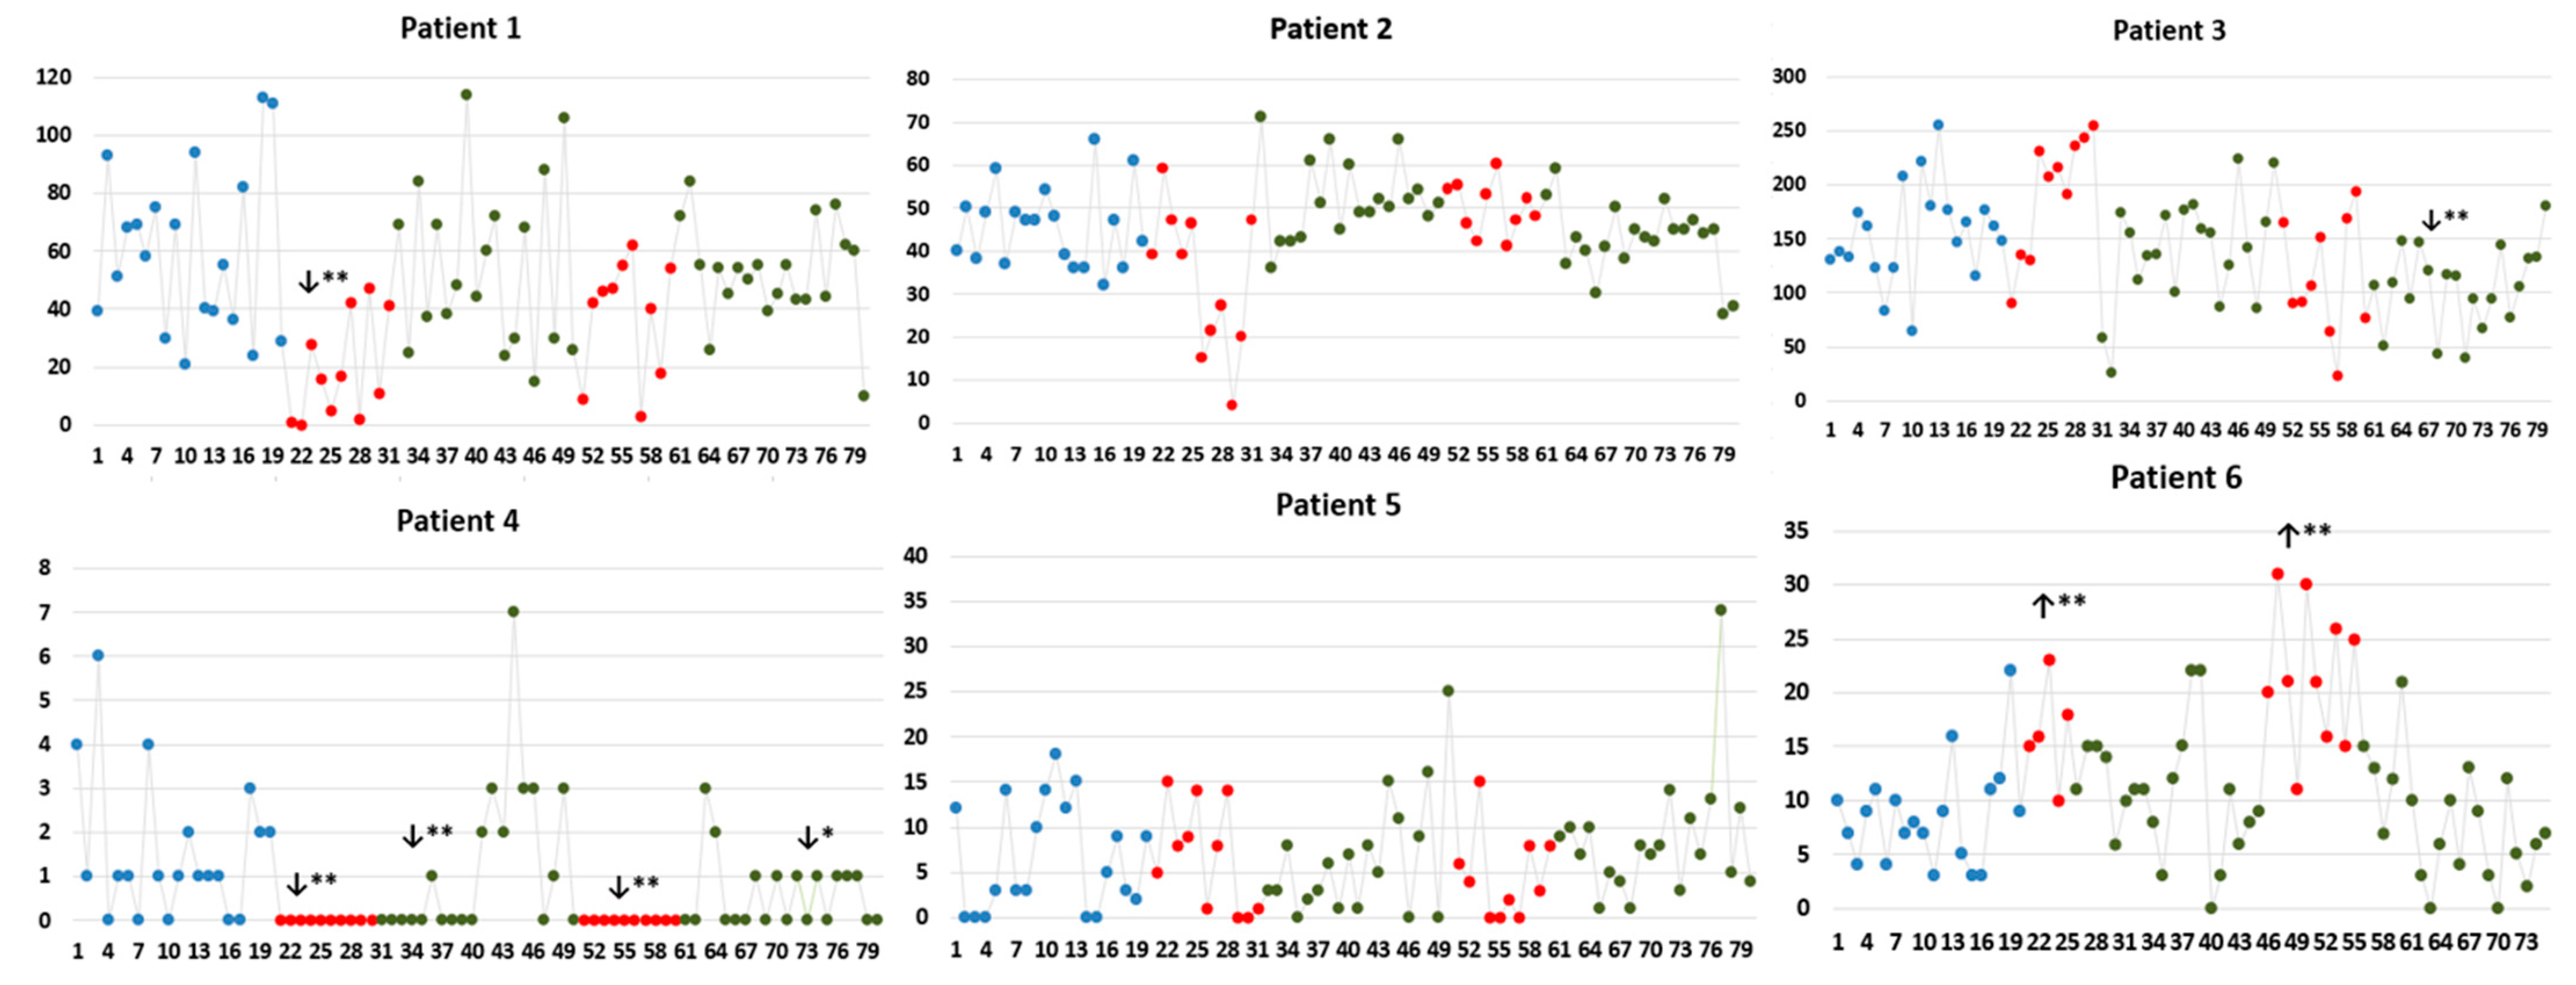

| Patient 1 | IED rate (IED/minute); median (IQR) | ||||||

| IED localizations | B | S1 | PS1 | S2 | PS2 | ||

| 1st 10 min | 2nd 10 min | 1st 10 min | 2nd 10 min | ||||

| OF | 9 (15.75) | 0 (2.25) ↓ (p = 0.004) | 15.50 (9.75) | 20.50 (16) ↑ (p = 0.023) | 17 (19.17) | 22 (18) ↑ (p = 0.013) | 16.50 (18.50) |

| aINS | 1 (3.75) | 0 (0.25) ↓ (p = 0.042) | 0 (0) ↓ (p = 0.003) | 0 (0) ↓ (p = 0.003) | 0 (0) ↓ (p = 0.003) | 0 (0) ↓ (p = 0.003) | 0 (0) ↓ (p = 0.003) |

| OF-aINS | 31 (37.75) | 7 (21.75) ↓ (p = 0.025) | 35 (38.75) | 12.50 (60) | 22.5 (7.0) | 32.5 (17) | 36 (27.25) |

| Patient 2 | IED rate (IED/minute); median (IQR) | ||||||

| IED localizations | B | S1 | PS1 | S2 | PS2 | ||

| 1st 10 min | 2nd 10 min | 1st 10 min | 2nd 10 min | ||||

| T-P operculo-pINS | 46 (13.75) | 24 (15.75) ↓ (p = 0.006) | 45 (20.5) | 51 (7.50) ↑ (p = 0.007) | 49 (8.25) | 37 (14) | 41.50 (6.5) |

| lateral T | 0 (1) | 0 (0) | 0 (0) | 0 (0) | 0 (2) | 0 (1) | 0 (0) |

| Synchronous | 2 (3.75) | 0 (1) ↓ (p = 0.03) | 0 (1) ↓ (p = 0.03) | 0 (2.25) | 0 (1) ↓ (p = 0.03) | 5 (9.25) ↑ (p = 0.038) | 2 (3.25) |

| Patient 3 | IED rate (IED/minute); median (IQR) | ||||||

| IED localizations | B | S1 | PS1 | S2 | PS2 | ||

| 1st 10 min | 2nd 10 min | 1st 10 min | 2nd 10 min | ||||

| aINS | 113 (54.75) | 126 (92.25) | 106.50 (8.25) | 123.5 (67.26) | 67 (86.5) | 94 (52.5) | 81.5 (60.6) |

| IFG-aINS | 32 (36.5) | 60 (40) | 20 (20.75) | 29.5 (34.75) | 29.5 (19) | 18 (14.25) ↓ (p = 0.022) | 22 (21.25) |

| STG-aINS | 0 (4.25) | 0 (2) | 0 (4.25) | 0 (1.75) | 0 (1.25) | 0 (0) | 0 (2.0) |

| synchronous | 1 (11.75) | 13 (41) | 0 (1) | 0 (2) | 0 (5.25) | 0.5 (3.25) | 0 (1.25) |

| Patient 4 | IED rate (IED/minute); median (IQR) | ||||||

| IED localizations | B | S1 | PS1 | S2 | PS2 | ||

| 1st 10 min | 2nd 10 min | 1st 10 min | 2nd 10 min | ||||

| T-P opercula-pINS | 1.6 (2.75) | 0 (0) ↓ (p < 0.001) | 0 (0) ↓ (p < 0.001) | 2 (3.0) | 0 (0) ↓ (p < 0.001) | 0 (1.25) | 0.5 (1.0) ↓ (p = 0.040) |

| Synchronous | 0 (0) | 0 (0) | 0 (0) | 0 (0.25) | 0 (0) | 0 (0) | 0 (0) |

| Patient 5 | IED rate (IED/minute); median (IQR) | ||||||

| IED localizations | B | S1 | PS1 | S2 | PS2 | ||

| 1st 10 min | 2nd 10 min | 1st 10 min | 2nd 10 min | ||||

| lateral T | 2.5 (4.5) | 1.5 (7.25) | 0 (1.25) ↓ (p = 0.010) | 3 (5.5) | 2.5 (5.75) | 2 (4.25) | 4.5 (5.0) |

| lateral prefrontal | 0 (1) | 0 (0.25) | 1.5 (2.25) ↑ (p = 0.005) | 0.5 (2.25) | 0 (1.0) | 0.5 (2.0) | 0.5 (2.0) |

| Synchronous | 1 (6.5) | 0 (1.25) | 0 (1.25) | 3 (5.5) | 0 (0.75) ↓ (p = 0.044) | 2 (4.25) | 1 (4) |

| Patient 6 | IED rate (IED/minute); median (IQR) | ||||||

| IED localizations | B | S1 | PS1 | S2 | PS2 | ||

| 1st 10 min | 2nd 10 min | 1st 10 min | 2nd 10 min | ||||

| OF | 6.50 (4.50) | 16 (7.0) ↑ (p = 0.001) | 8 (6.50) | 9 (10.75) | 21 (11.25) ↑ (p < 0.001) | 8 (8.25) | 5 (5) |

| pINS | 0 (1) | 0 (0) | 0 (1) | 0 (0) | 0 (0) | 0 (0.25) | 0 (0) |

| Posterior T | 1.5 (3) | 0 (3) | 3.5 (4.25) | 1.5 (3.25) | 0 (0.75) | 0.5 (3.5) | 0 (2) |